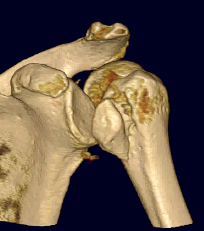

CT scan

Confirms dislocation

Reverse Hill Sachs

Humeral head defect

- caused by impaction of anterior humeral head on posterior glenoid

- intra-articular

- measured as a percentage of the articular surface

Lesser tuberosity fractures

Posterior glenoid fractures / bony bankart